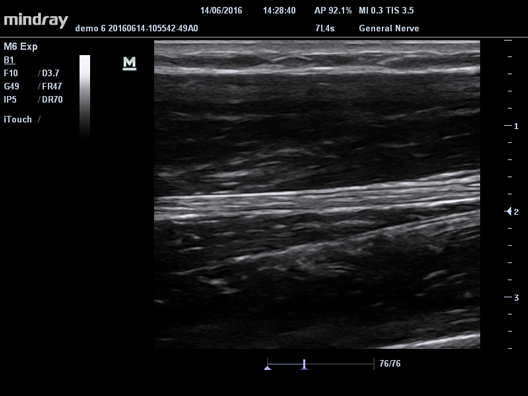

iBeam

Составное многолучевое сканирование. С помощью этой функции можно соединить отдельные фрагменты, полученные под различными углами, в единое изображение. В результате чего достигается повышенное контрастное разрешение и улучшенная визуализация.

iBeam

Составное многолучевое сканирование. С помощью этой функции можно соединить отдельные фрагменты, полученные под различными углами, в единое изображение. В результате чего достигается повышенное контрастное разрешение и улучшенная визуализация.